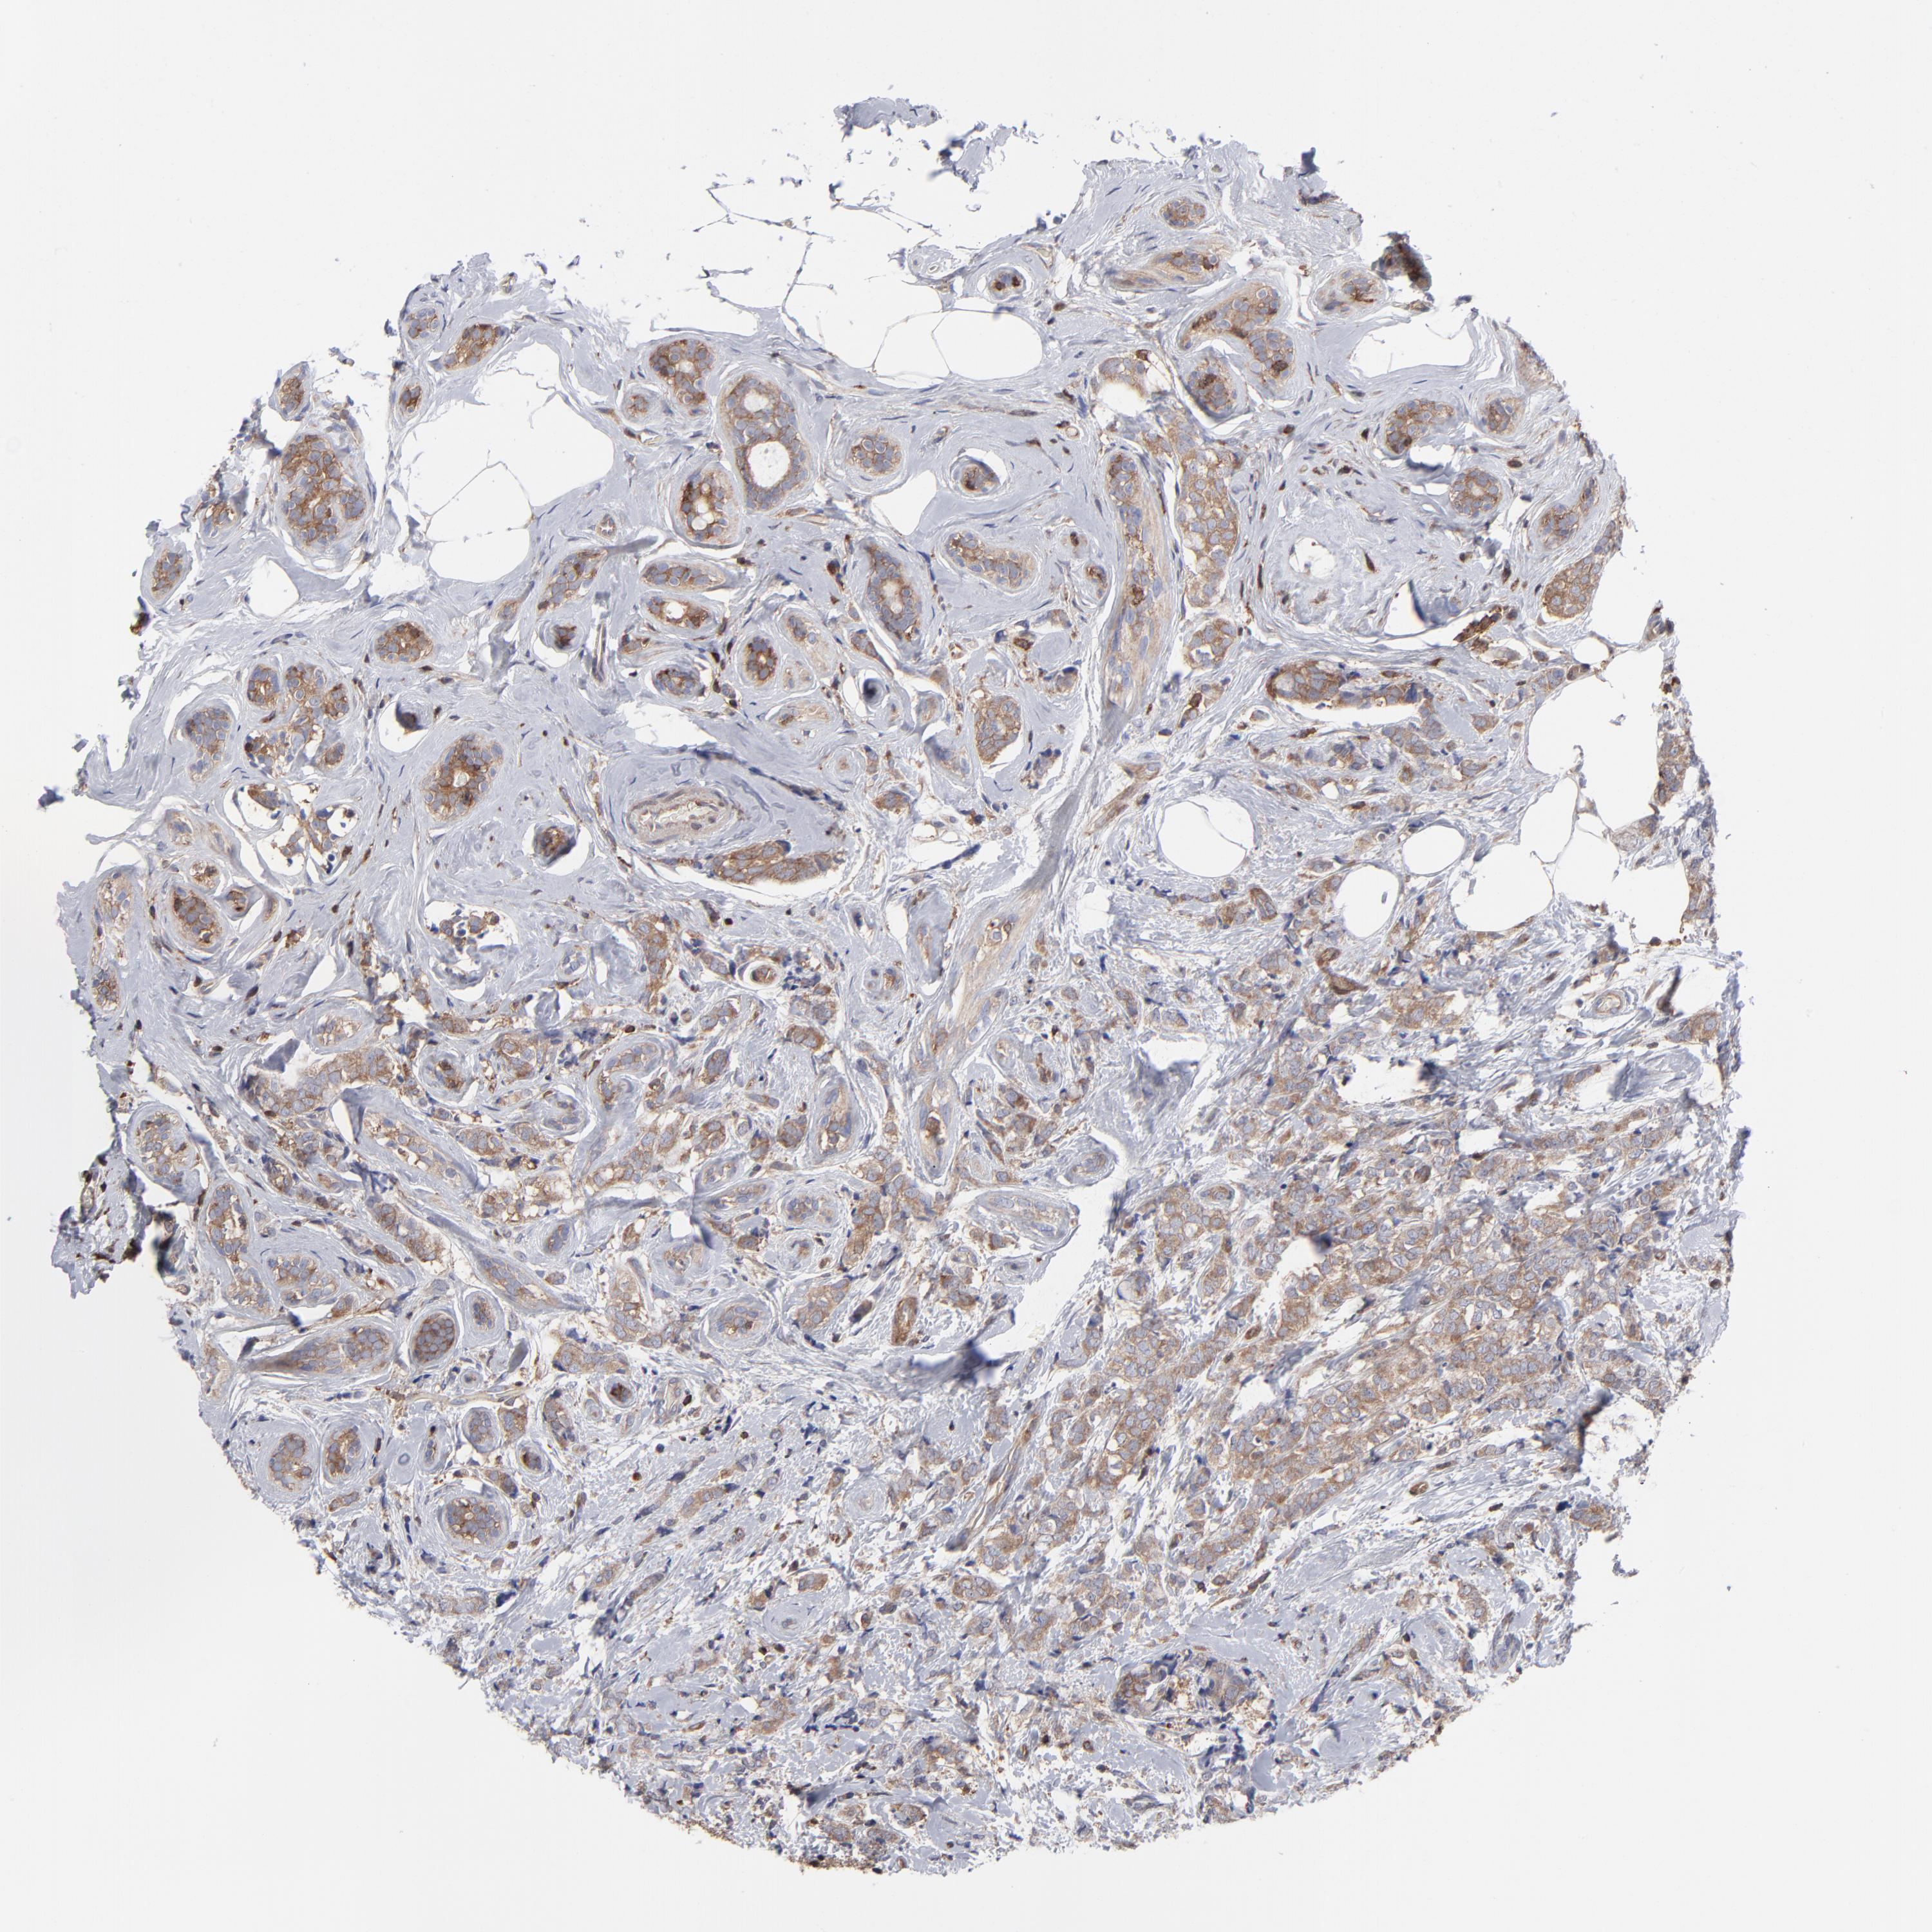

CANCER BREAST CANCER Show tissue menu

BRCA TCGA BRCA VALIDATION PROTEIN EXPRESSION